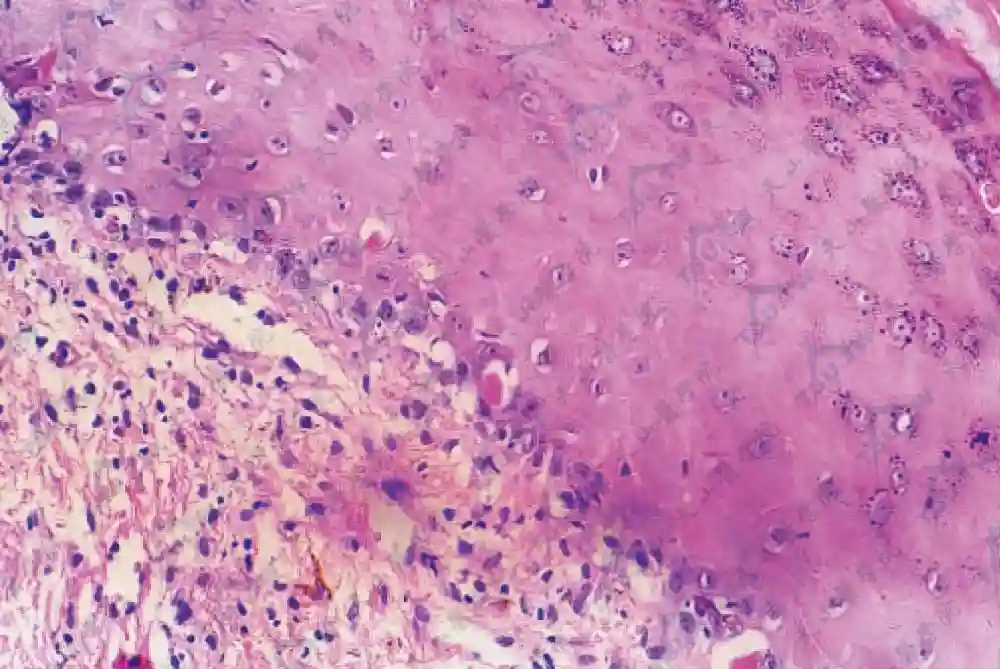

移植物抗宿主病(GVHD)是由于移植后异体供者移植物中的T淋巴细胞,经受者发动的一系列“细胞因子风暴”刺激,大大增强了其对受者抗原的免疫反应,以受者靶细胞为目标发动细胞毒攻击,其中皮肤、肝及肠道是主要的靶目标。急性移植物抗宿主病的发生率为30%~45%,慢性者发生率低于急性。